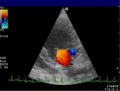

Die Aussagekraft der Sonografie kann erheblich durch die Anwendung des Doppler-Effekts erhöht werden. Man unterscheidet eindimensionale Verfahren (Pulsed-Wave-Doppler, Continuous-Wave-Doppler, auch als D-mode bezeichnet) von zweidimensionalen, farbkodierten Anwendungen (Farbdoppler – F-mode). Die Kombination B-Bild mit Pulsed-Wave-Doppler (PW-Doppler) nennt man auch Duplex.[4]

Doppler-Verfahren werden benutzt zur Bestimmung von Blutfluss-Geschwindigkeiten, zur Entdeckung und Beurteilung von Herz(klappen)fehlern, Verengungen (Stenosen), Verschlüssen oder Kurzschlussverbindungen (Shunts).

Bei der farbkodierten Doppler-Sonografie wird für einen großen Bereich eines konventionellen Ultraschallbildes (Color-Window) die örtliche Doppler-Frequenz (= mittlere Flussgeschwindigkeit) und deren Schwankungsbreite bestimmt. Damit möchte man die Turbulenz der Strömung abschätzen. Aufgrund der statistischen Bewegungen der Streuteilchen ist die Schwankungsbreite der Fließgeschwindigkeit jedoch stets größer als die Turbulenz. Das Ergebnis wird in Falschfarben auf dem B-Bild überlagert, also in Farbtönen von rot und blau für verschiedene Blutgeschwindigkeit und grün für Turbulenz. Hierbei steht üblicherweise die Farbe Rot für Bewegung auf den Schallkopf zu, während mit blauen Farbtönen Flüsse weg von der Sonde codiert werden. Bereiche der Geschwindigkeit 0 werden durch die Elektronik unterdrückt.

-

Anwendung des Doppler-Verfahrens bei einer Herzuntersuchung: Mitralklappeninsuffizienz -

Farb-Doppler und PW-Doppler. Innerhalb der Stenose ist wegen der hohen Flussgeschwindigkeit und des resultierenden Alias-Effekts die Geschwindigkeit in Blau kodiert. -